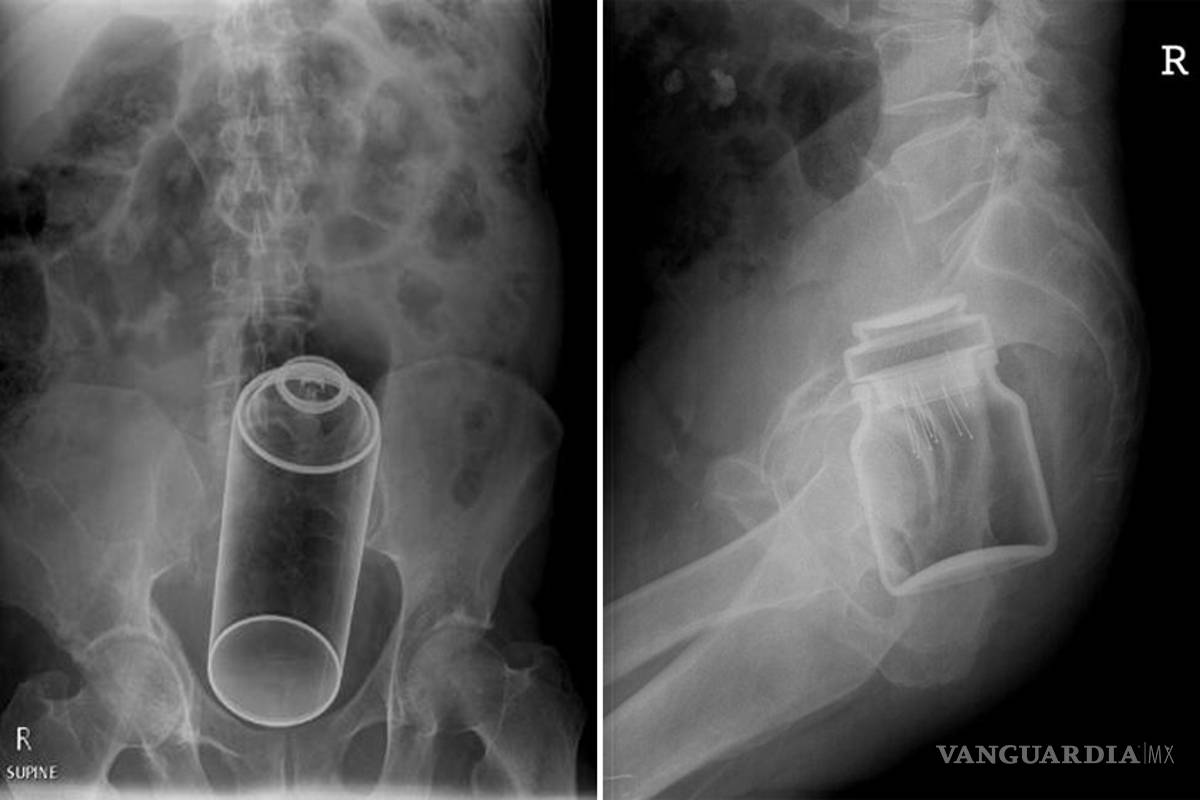

Radiopaedia.org tiene una sección especial de objetos encontrados en dicha zona del cuerpo, la cual es editada por dos doctores australianos. En ella se muestran radiografías de infortunadas personas que terminaron en salas de emergencia con objetos extraños dentro de ellos.

Entre los objetos encontrados dentro están botellas, vegetales, dildos, una cola de cerdo congelada, desodorantes, un frasco de café instantáneo o paquetes con droga.

La mayoría de los objetos llegan a esos lugares como resultado de algún episodio sexual que terminó muy mal y la mayoría son removidos mediante extracción o generando presión en el abdomen.